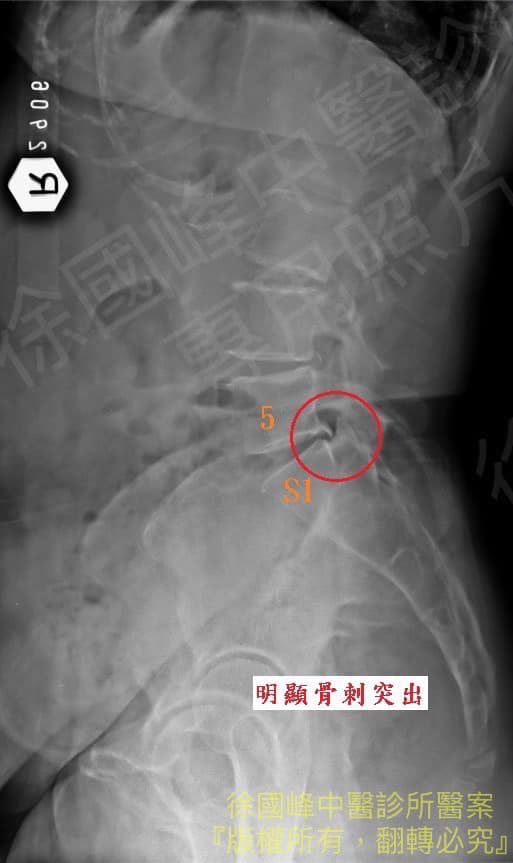

X光跟核磁共振都顯示有骨刺跟椎間盤突出,但並不特別嚴重,但為什麼會那麼痛,還痛到每天吃兩次止痛藥,答案是剛剛好卡住神經根,又發現患者髖關節張力過大,這種情況會讓患者雖然核磁共振看起來都沒有什麼大問題,但是走路一段時間會因為髖關節的張力拉扯到腰椎的腰大肌,進一步讓神經根拉扯

1.腰椎核心肌群萎縮

2.L5S1輕微椎間盤突出